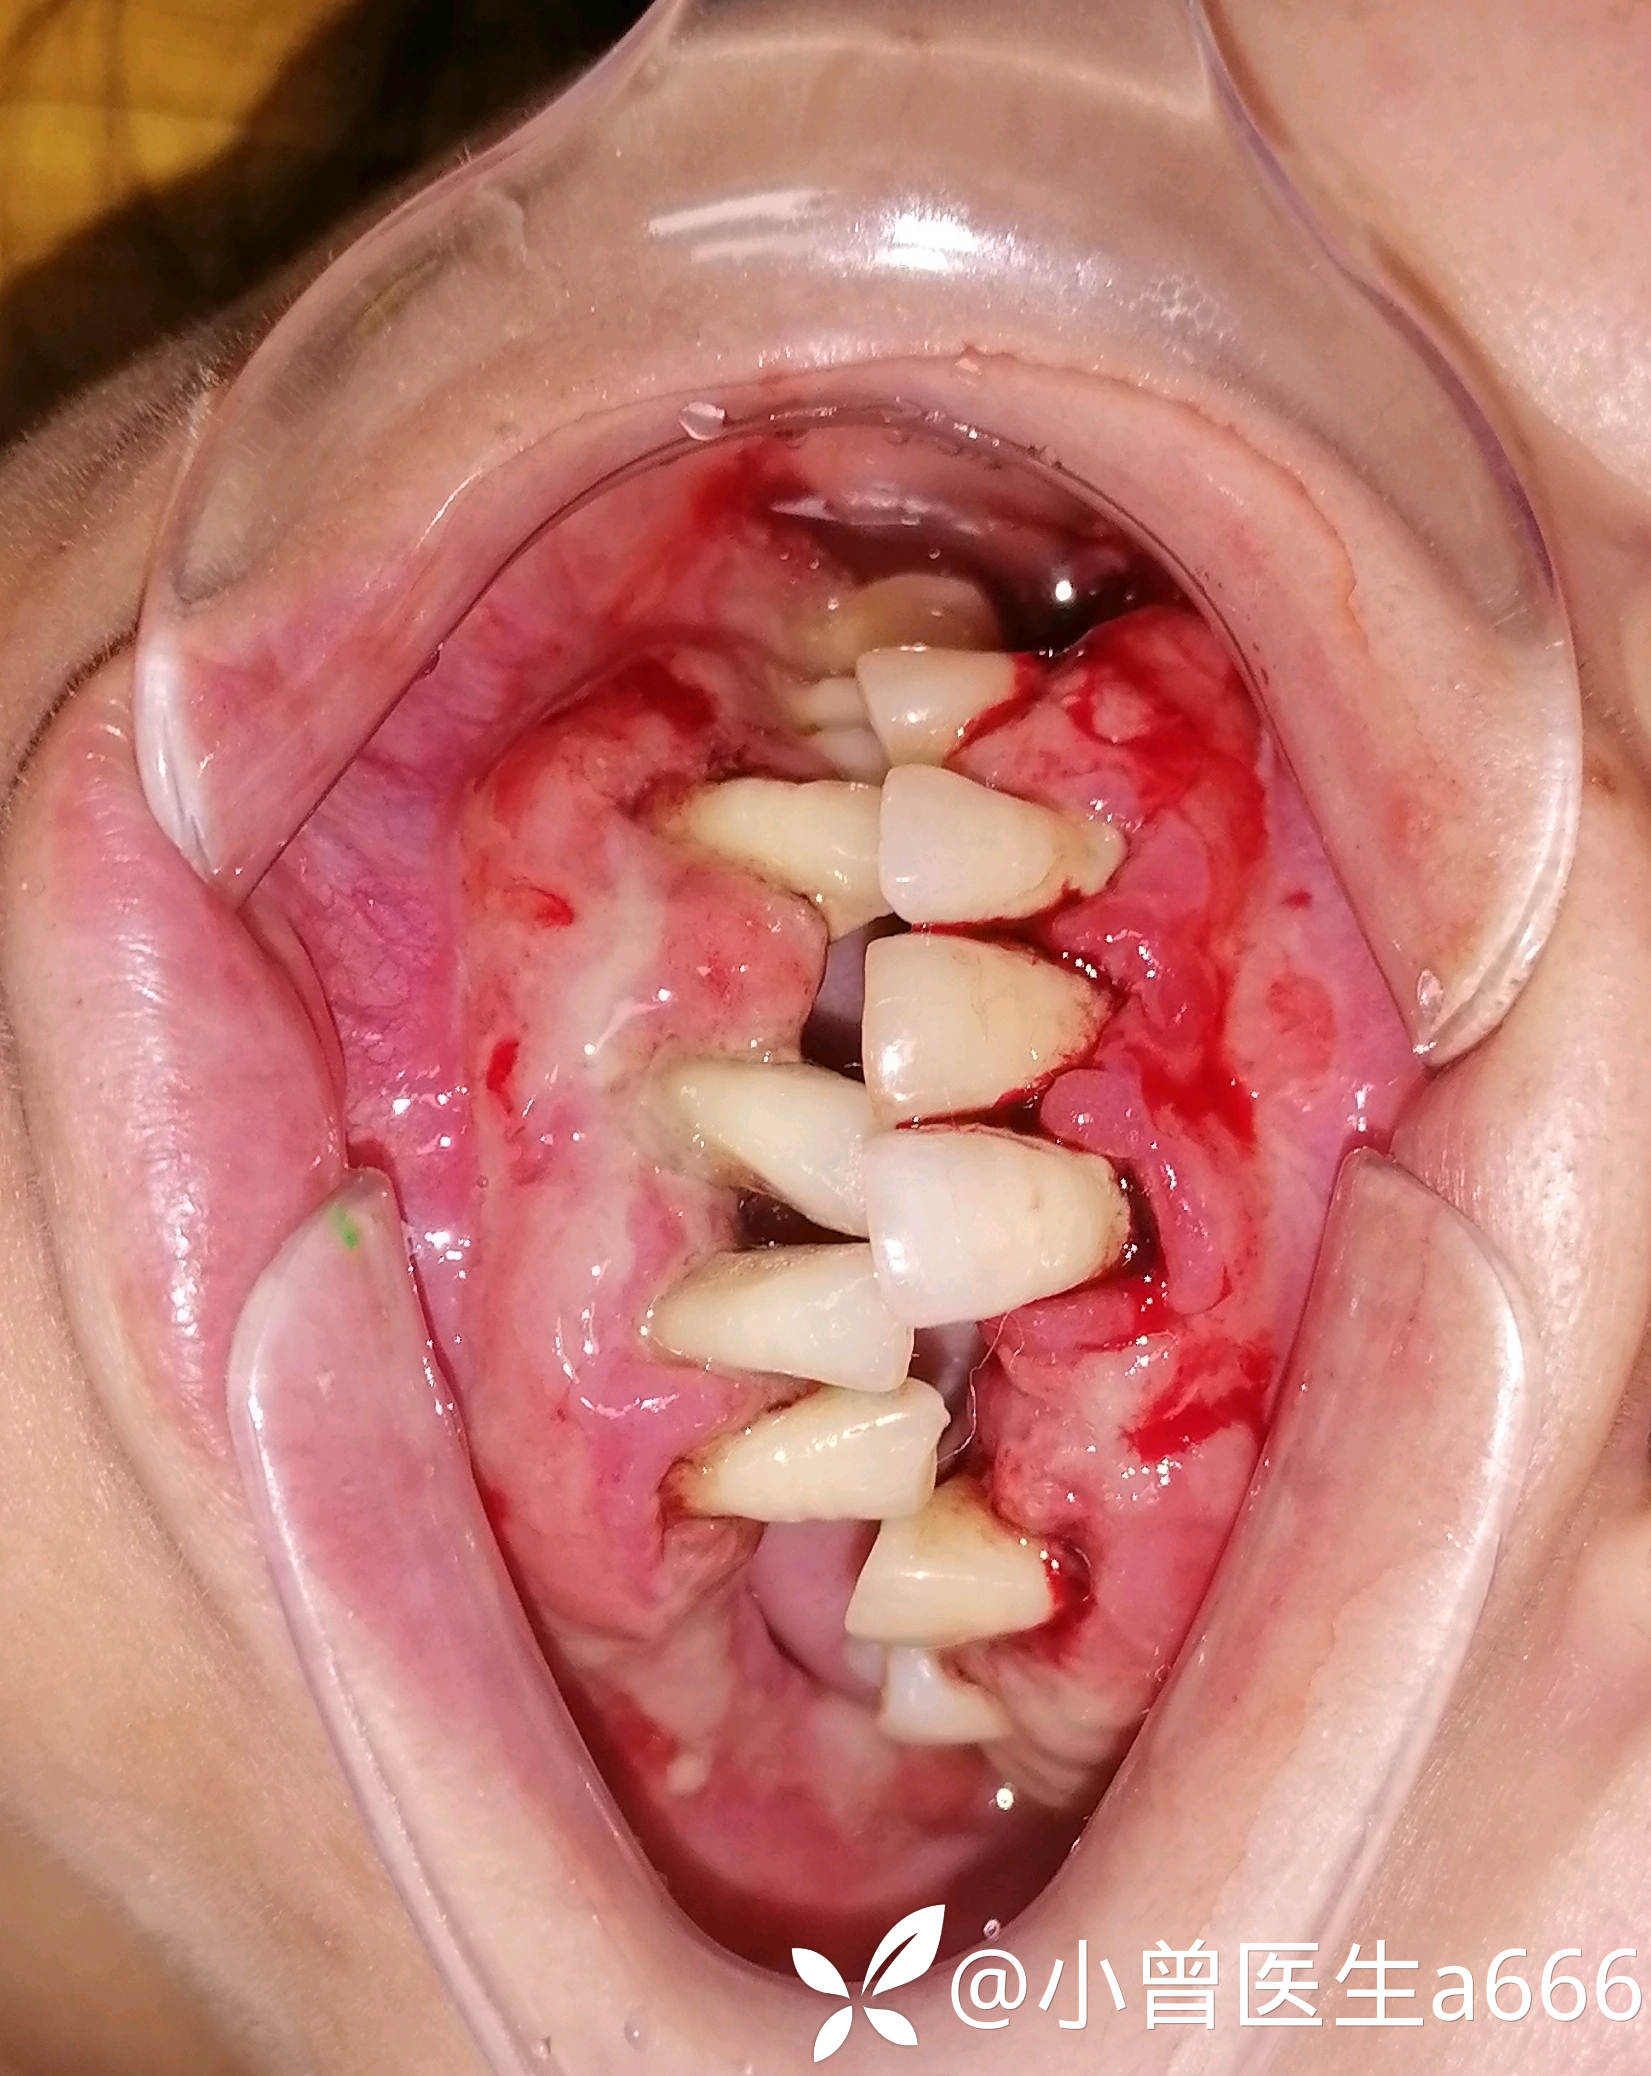

体格检查:全口牙龈红肿,探诊出血(+++),牙龈大面积溃疡溢脓,可探及深牙周袋,牙龈质软,牙龈退缩牙根暴露,见少量牙结石及软垢。牙龈牙齿检查未见疼痛不适。41缺失,41处牙龈肿胀增生至切1/3—1/2。视诊见下眼睑苍白无血色,皮肤暗黄,可见双臂皮肤斑点(患者自诉是过敏而致)

临床诊断:系统性疾病型牙周炎?